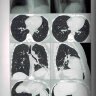

Примеры страниц из книги "Заключения в торакальной компьютерной томографии. Симптом, синдром, диагноз" - А. А. Сперанская